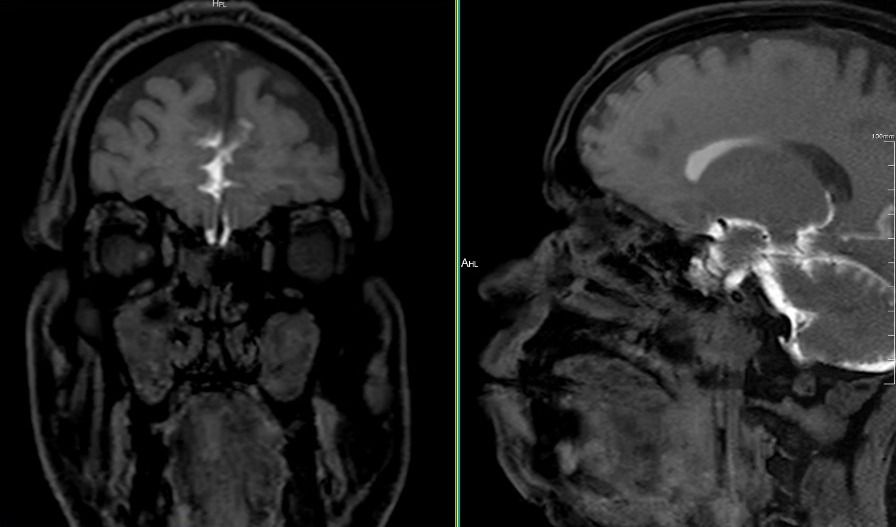

A 48-year-old male presented with a clinical suspicion of cerebrospinal fluid (CSF) rhinorrhea, characterized by persistent right-sided nasal discharge.

The study utilized a comprehensive Digital MRI Cisternography protocol on an advanced high-field system.

- Pre-contrast Sequences: Axial DWI, T2 STIR, Fat-saturated T1 (coronal and sagittal), T2 FSE coronal, and high-resolution T2 SPACE sequences for detailed anatomical assessment of the skull base.

- Post-contrast Dynamics: Performed following intrathecal gadolinium administration, utilizing T1-weighted fat-saturated images in sagittal and coronal planes at 1-hour and 2-hour intervals.

- Delayed Imaging: An additional delayed scan was performed at the 36–38 hour mark to detect intermittent or slow-flow leaks.

- CSF Leak Assessment: No continuous T1 hyperintense CSF tract was identified extending from the basal subarachnoid spaces across the cribriform plate or central skull base into the sinonasal cavity.

- Delayed Phase: No evidence of contrast extravasation was noted on scans acquired up to 38 hours post-injection.

- Sinonasal Anatomy: Moderate mucosal thickening in bilateral maxillary and ethmoid sinuses, causing obstruction of the right ostiomeatal complex. Minimal rightward nasal septal deviation and bilateral inferior turbinate hypertrophy.

- Intracranial Findings: Normal brain parenchyma with no evidence of cephalocele or focal lesions.